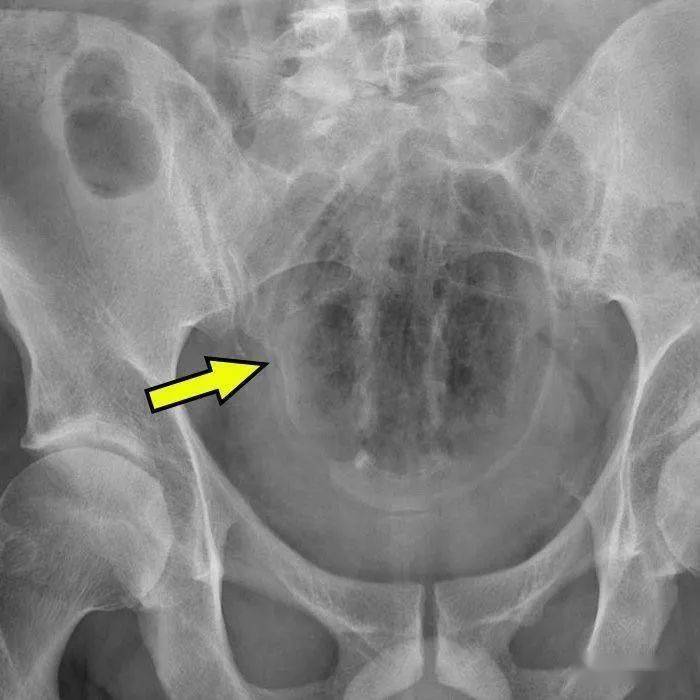

▷圆茄子研究案例的段子手医生表示:圆茄子的形状意味着 , 一旦它的赤道 (也就是最宽的部分)挤进了肛门边缘 ,它就会有往上窜的趋势 。而当这种情况发生的时候 , 嗯…就意味着你要去急诊室了 。